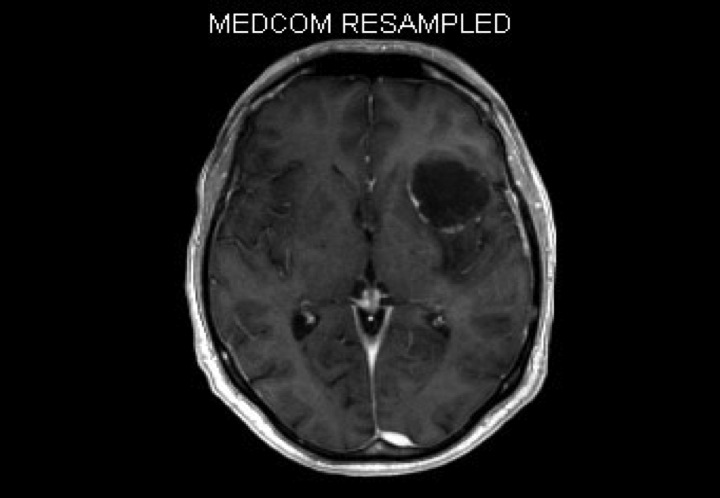

Maurer mit plötzlichen Sprachstörungen

ICD: C43.9

ICD: C71.9

ICD: C79.3

53-jähriger Maurer. Er ist noch nie beim Arzt gewesen und hat auch die empfohlenen Vorsorgeuntersuchungen nie durchführen lassen.

Seit der vergangenen Woche hat er Schwierigkeiten beim Sprechen bemerkt.